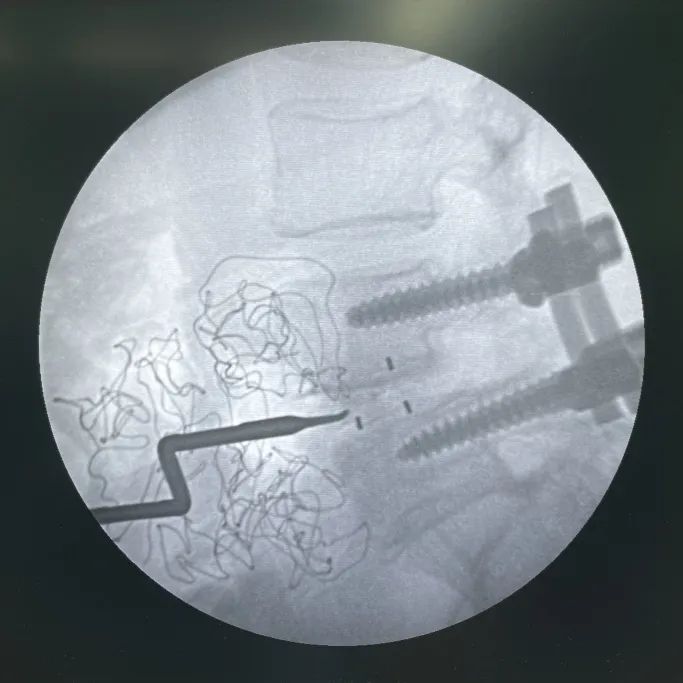

術中影像

- 患者右側臥位,透視確認皮膚(fu)切口區域

- 切皮暴露(lu),透(tou)視確認手術節(jie)段

- 最終透視